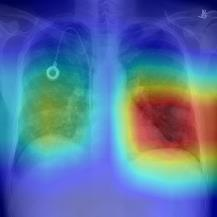

Thoracic disease detection from chest radiographs using deep learning methods has been an active area of research in the last decade. Most previous methods attempt to focus on the diseased organs of the image by identifying spatial regions responsible for significant contributions to the model's prediction. In contrast, expert radiologists first locate the prominent anatomical structures before determining if those regions are anomalous. Therefore, integrating anatomical knowledge within deep learning models could bring substantial improvement in automatic disease classification. This work proposes an anatomy-aware attention-based architecture named Anatomy X-Net, that prioritizes the spatial features guided by the pre-identified anatomy regions. We leverage a semi-supervised learning method using the JSRT dataset containing organ-level annotation to obtain the anatomical segmentation masks (for lungs and heart) for the NIH and CheXpert datasets. The proposed Anatomy X-Net uses the pre-trained DenseNet-121 as the backbone network with two corresponding structured modules, the Anatomy Aware Attention (AAA) and Probabilistic Weighted Average Pooling (PWAP), in a cohesive framework for anatomical attention learning. Our proposed method sets new state-of-the-art performance on the official NIH test set with an AUC score of 0.8439, proving the efficacy of utilizing the anatomy segmentation knowledge to improve the thoracic disease classification. Furthermore, the Anatomy X-Net yields an averaged AUC of 0.9020 on the Stanford CheXpert dataset, improving on existing methods that demonstrate the generalizability of the proposed framework.